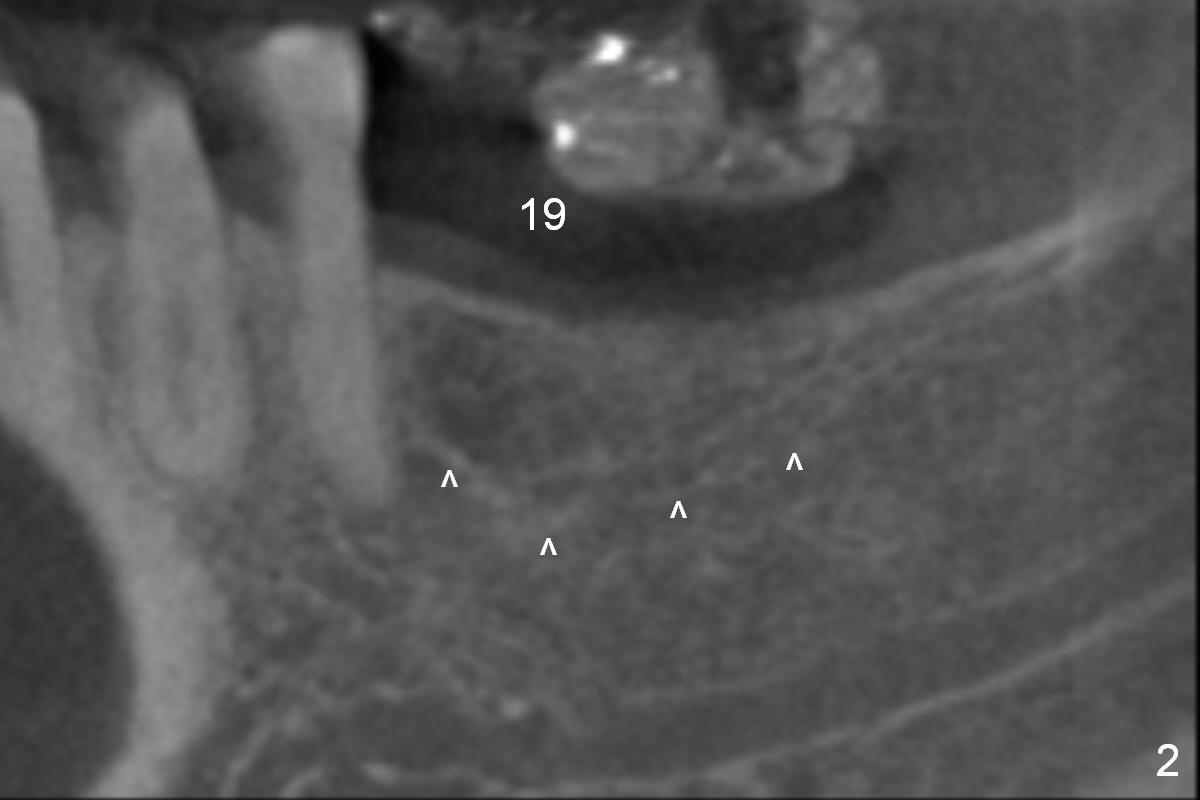

CBCT 3-D image taken with scan stents at the sites of #18 and 19 shows 2 Mental Foramina (Fig.1 *) in the left mandible.  Both sagittal (Fig.2) and coronal (Fig.3) sections show low density at the crest of #19 of a 55-year-old man (arrowheads).  The crest is also narrow.  After making an initial osteotomy through the stent (Fig.4 red arrow), remove the latter (Fig.5).  Ridge split is initiated with wheel saws (Fig.6 blue line).  The osteotomy is enlarged with bone expanders (Fig.7 green circle) with ridge split (blue lines).  Finally an implant is placed (Fig.8 pink circle) with placement of bone graft in the space of the ridge split (yellow circles).